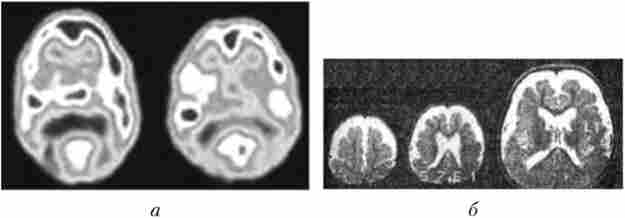

Мал. 4.28. Методи дослідження головного мозку:

а - позитронно-емісійна томографія (ПЕТ) мозку при вивченні міжпівкульна асиметрії. Активація кровотоку в лобових частках лівого і правого півкуль при розумової діяльності; 6 - магнітно-резонансна томографія (МРТ). Наслідки внутрішньоутробного ураження ЦНС: атрофія білої речовини близько шлуночків мозку і кори лобових і тім'яних часток півкуль

Позитронно-емісійна томографія мозку (ПЕТ) дає можливість побачити і зареєструвати мозковий кровотік і метаболізм активних ділянок мозку, а також отримати їх просторове зображення при виконанні різних функцій, наприклад мовної, зорової та ін. (Рис. 4.28). Для цього людині вводять в кровоносне русло ізотопи, які з током крові потрапляють в головний мозок. За допомогою спеціальних датчиків визначається кровотік в активізованих ділянках мозку, і комп'ютер видає результат.